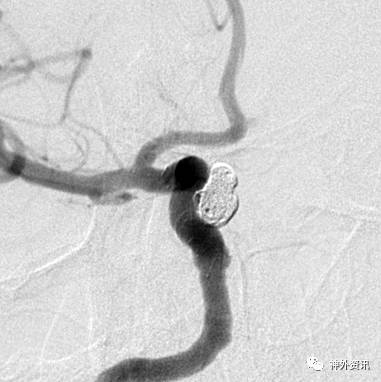

病例一